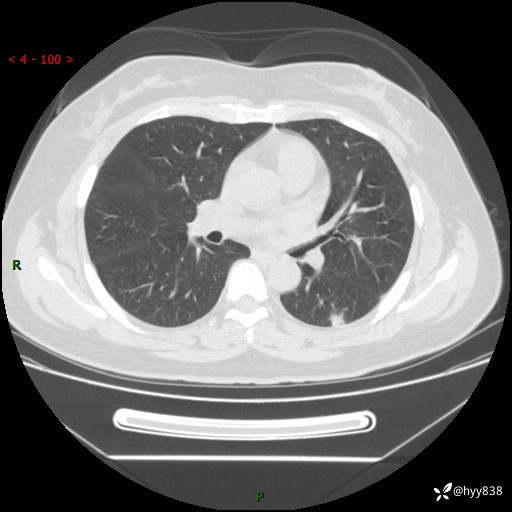

胸部CT复查+增强(2024.6)